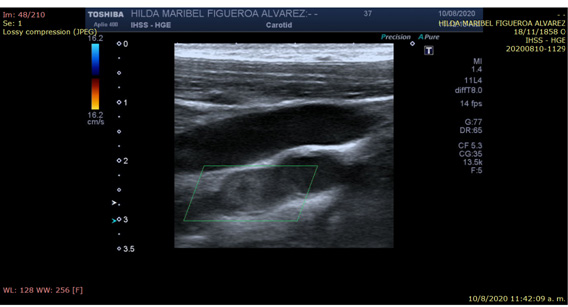

Se solicitan pruebas complementarias (Tabla 1); Tomografía cerebral en fase simple, sin evidencia de lesiones focales y / o difusas. Sin embargo, el Doppler carotídeo de la USG describe la ausencia de flujo en la arteria carótida interna izquierda (ACI) debido a la presencia de material ecogénico inmediatamente en la bifurcación de la arteria carótida común (Fig. 1; video ultrasonido Doppler de la carotida).

Figura 1 Ecografía Doppler carotídeo. No hay evidencia de flujo al aplicar Doppler color o espectral debido a la presencia de material ecogénico en su interior. (Recuadro verde)